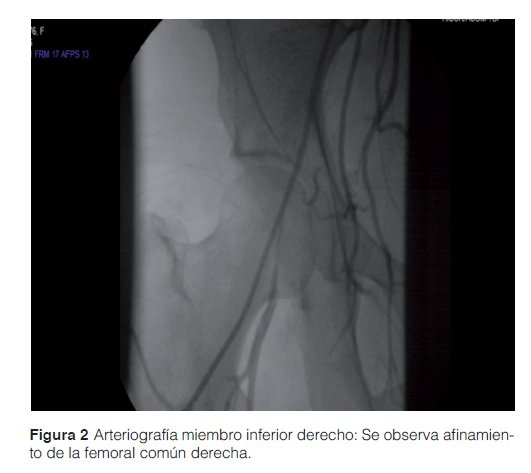

Mujer 39 años, con antecedentes previos de embarazo complicado con eclampsia. No presenta abortos previos. La paciente es ingresada en el centro de salud de su comunidad por lesiones en pie derecho de 7 meses de evolución que inicia en forma de ampollas dolorosas en tercio inferior de la pierna y dorso de pie derecho, con aumento progresivo de tamaño y ulceración posterior. Durante el ingreso presenta necrosis del primer dedo del pie derecho (Figura 1), por lo que se procede a la epidermonecrosectomía con toma de biopsia. Ingresa a cargo del Servicio de reumatología para estudio de dicha patología.

Al realizar el interrogatorio funcional la paciente niega fiebre, pérdida de peso, artralgias u otro síntoma acompañante. Niega hábitos tóxicos. Al examen físico se constató una presión arterial media en miembro superior derecho de 140/90 mmHg y en miembro superior izquierdo de 135/90 mmHg, en miembro inferior derecho de 130/90 mmHg y en miembro inferior izquierdo de 135/80 mmHg. Frecuencia cardíaca de 117 latidos/minuto y frecuencia respiratoria de 20 por minuto. Peso de 81,6 kg. No se palpan pulsos radiales, ni pedios ni tibial posterior ni poplíteo ni femoral, humeral apenas perceptible. No soplos. Ausencia del primer dedo del pie derecho. Se observaron 3 úlceras en sacabocados en dorso del mismo ambas de 4 cm y otra de 1 cm de diámetro, en tercio inferior de la pierna ipsilateral. Resto del examen sin particularidades. La biopsia previa al ingreso mostró una vasculitis leucocitoclástica y el cultivo fue negativo para BAAR. La ecocardiografía resultó normal. Se realizó una arteriografía de la arteria femoral superficial izquierda donde se constató trombosis en tercio inferior. La arteriografía del miembro inferior derecho (Figura 2) mostró un afinamiento de la femoral común derecha. En la Aortografía se observó ausencia de lesiones en el cayado aórtico, aorta descendente y abdominal. El Ecodoppler arterial mostró oclusión de ambas femorales superficiales, además de presentar oclusión de ambos miembros superiores por debajo del codo. Durante la estancia en sala recibió anticoagulación, cobertura antibiótica con piperacilina tazobactam dirigido a las lesiones. Se inició prednisona a 50 mg/día y azatioprina 50mg/día. Con mejoría de las lesiones. Actualmente se encuentra con 100 mg de azatioprina y 10 mg/día de prednisona. Durante su evolución tras tratamiento mostró mejoría de las lesiones ulcerosas en dorso y tercio inferior del miembro inferior derecho (Figura 3).